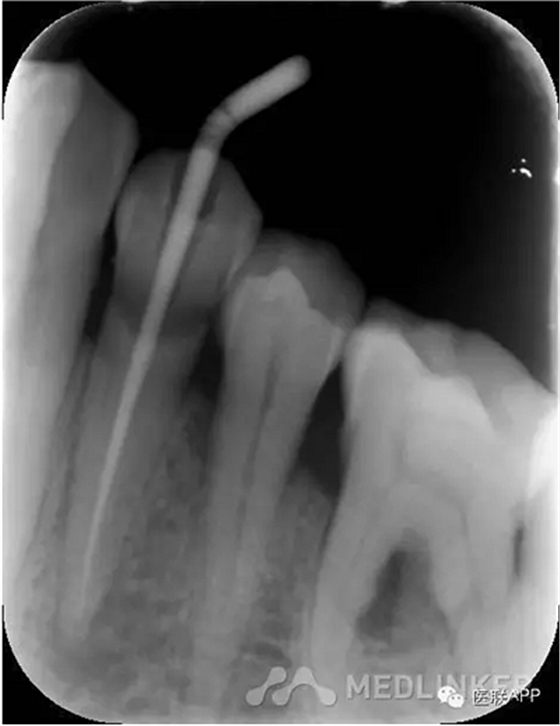

初診:頰側(cè)去腐,合面常規(guī)開(kāi)髓揭頂,拔髓,電測(cè)根長(zhǎng)WL=22mm,EDTA下手?jǐn)U+機(jī)擴(kuò)+protaper根備至F2,CR反復(fù)沖洗,干燥,Vitapex根充,ZOE暫封,約日復(fù)診。